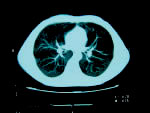

肺がんの多くは肺内の気管支の枝先、気管支末梢部にできるものが多く、症状がないまま進行します。早期の肺がんを見つけるには、従来の胸部X線検査に加え、マルチスライスCTで胸の断層写真を撮影するのが有効とされています。

マルチスライスCTとは

胸部全体をらせん状に連続撮影した超精細画像によって、ごく小さな初期の肺がんを早期に発見することが出来ます。 |

寝台に乗って検査し、寝台を下りるまでの所要時間は約5分です。